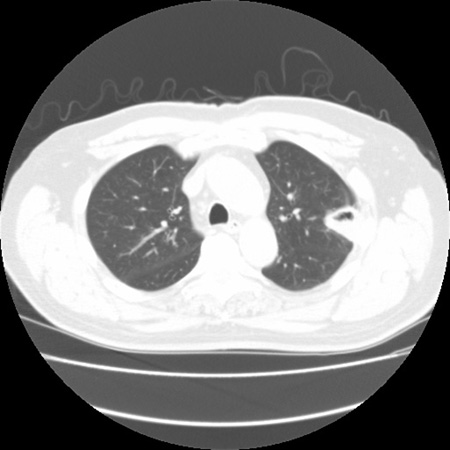

Sinal de "halo" em aspergilose pulmonar inicial

Do acervo do Dr. P. Chandrasekar; usado com permissão

Veja esta imagem em contexto nas seguintes seções: